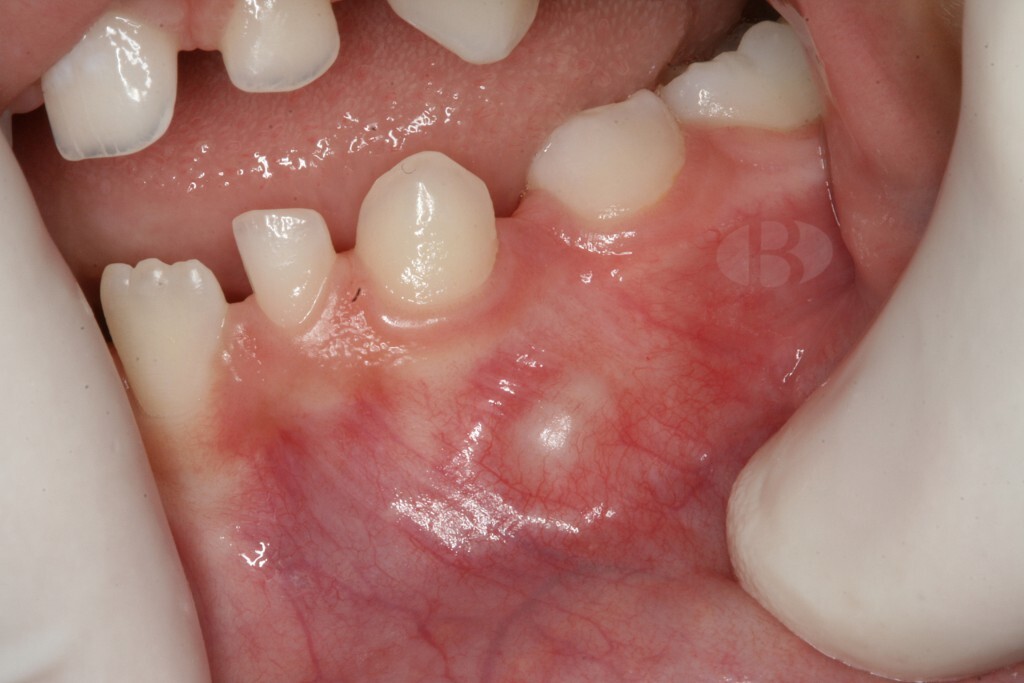

Phase 1: Gingivitis

Periodontitis and its precursor, gingivitis often go unnoticed until significant damage has already been done and in many cases – irreversible. Gingivitis is essentially inflammation of the gums, which in its turn is an effect of plaque buildup from inadequate oral hygiene. The bacteria in plaque produce toxins that can damage the gums and cause them to pull away from the teeth, forming pockets where more bacteria can accumulate. This vicious cycle leads to deepening of the pockets, and the gums starting to recede, exposing the roots of the teeth. This can cause sensitivity, pain, and eventually, tooth loss.

Genetics and personal habits such as smoking and poor oral hygiene can also contribute to the development of gingivitis and periodontitis.

Risks of leaving gingivitis untreated

Gum disease often goes undetected and, when untreated, can cause irreversible damage to soft tissue and bone. This leads to gum recession, jawbone deterioration and eventually to tooth loss.

Furthermore, studies link untreated gingivitis to a higher risk of cardiovascular disease, stroke, and diabetes. Poor oral health causes systemic inflammation and can lead to various health issues.

Progression to periodontitis

Periodontitis is a complex and mystifying process where certain types of bacteria cause damage to the gum tissue and bone structure supporting our teeth. As discussed it is usually preceded by gingivitis – the mild form of gum disease, that can progress to a more severe and damaging form.

Periodontitis begins with the accumulation of dental plaque, a biofilm composed of bacteria and extracellular matrix, on the teeth and gums. The bacteria in the plaque trigger the host’s immune response, leading to inflammation of the gingival tissue. The initial inflammatory response is characterized by increased blood flow and vascular permeability, which allows immune cells and proteins to infiltrate the affected tissue. In some individuals, the inflammatory response is not effectively resolved, resulting in persistent inflammation and destruction of the connective tissue and alveolar bone that support the teeth.

Early signs are often subtle, including bleeding gums, persistent bad breath, and slight discomfort while chewing. Without treatment, these symptoms worsen and more complications add up. Thus in the later stages of the disease, a person experiences bleeding and receding gums, deep pockets between the teeth and gums, loose teeth, changes in bite or tooth alignment, pus around the teeth and gums.